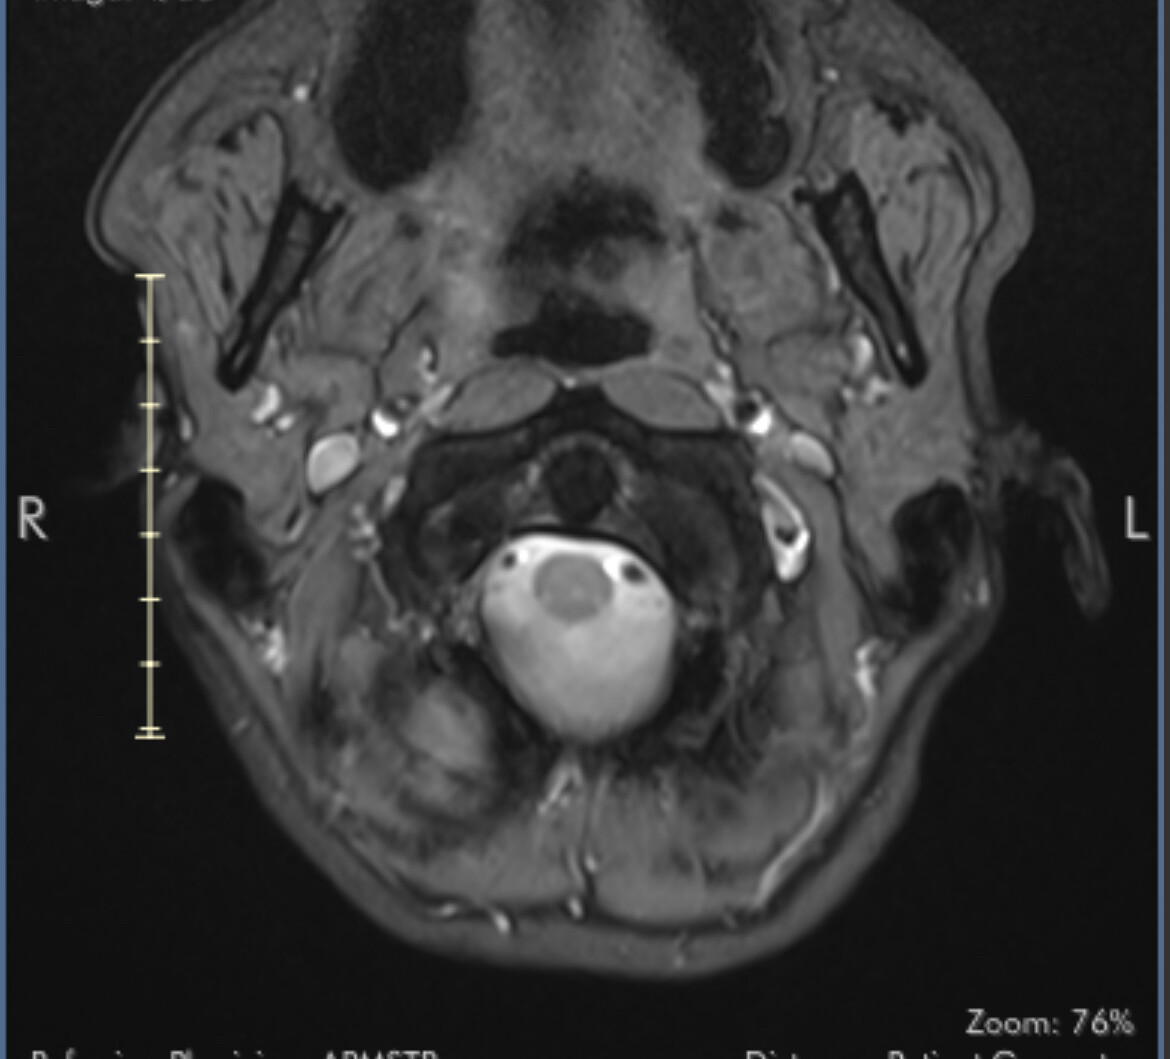

First stage of diagnosis - MRI images

I’ve uploaded some images now. I know they aren’t ideal but I’ll hopefully get my hands on the CT angiogram I had at A&E soon.

I marked the images for you and marked the IJV.

So you can see how the IJV passes by the transverse processes of C1 which are compressing. In this position the right IJV does not have severe compression, but in Figure 2 you can see that the left IJV is almost invisible, and in the other images there is significant narrowing.

On MRI, it is very difficult to see the styloid processes.